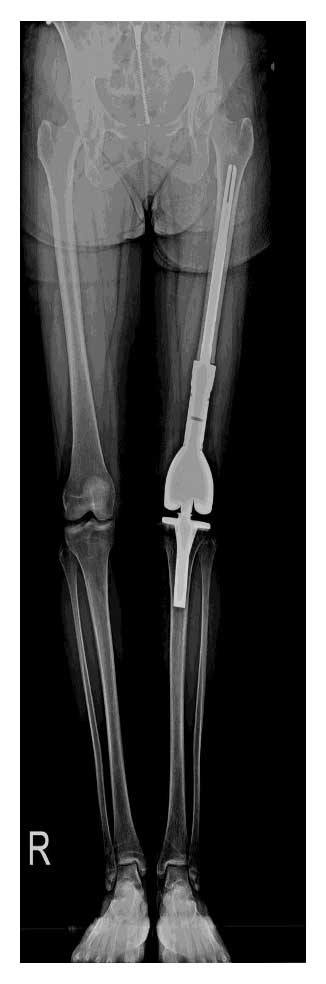

Hastaya kemoterapi sonrasında geniş rezeksiyon uygulanarak tümörlü bölge tamamen çıkarıldı. Eksize edilen kemik bölgesi distal femur tümör protezi ile rekonstrükte edilerek diz ekleminin stabilitesi ve fonksiyonu korundu.

Ameliyat Sonrası: Röntgende rezeksiyon sonrası uygulanan distal femur tümör protezi görülmekte.